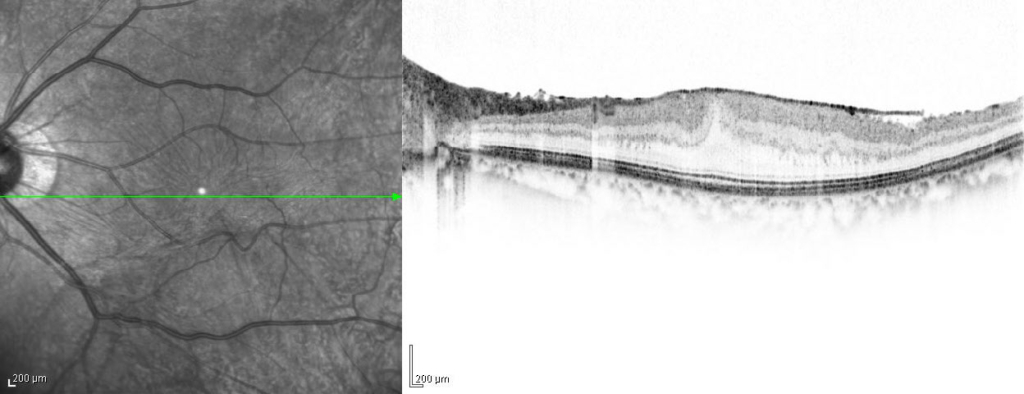

黄斑耳側の網膜表面に膜組織による高反射がみられ、血管が蛇行し偏位がみられる。

ERMを示す高反射が網膜前面にみられ、皺壁を形成している。黄斑網膜は肥厚し、中心窩は外顆粒層の挙上により三角形に隆起している。

黄斑耳側の網膜表面に膜組織による高反射がみられ、血管が蛇行し偏位がみられる。

ERMを示す高反射が網膜前面にみられ、皺壁を形成している。黄斑網膜は肥厚し、中心窩は外顆粒層の挙上により三角形に隆起している。